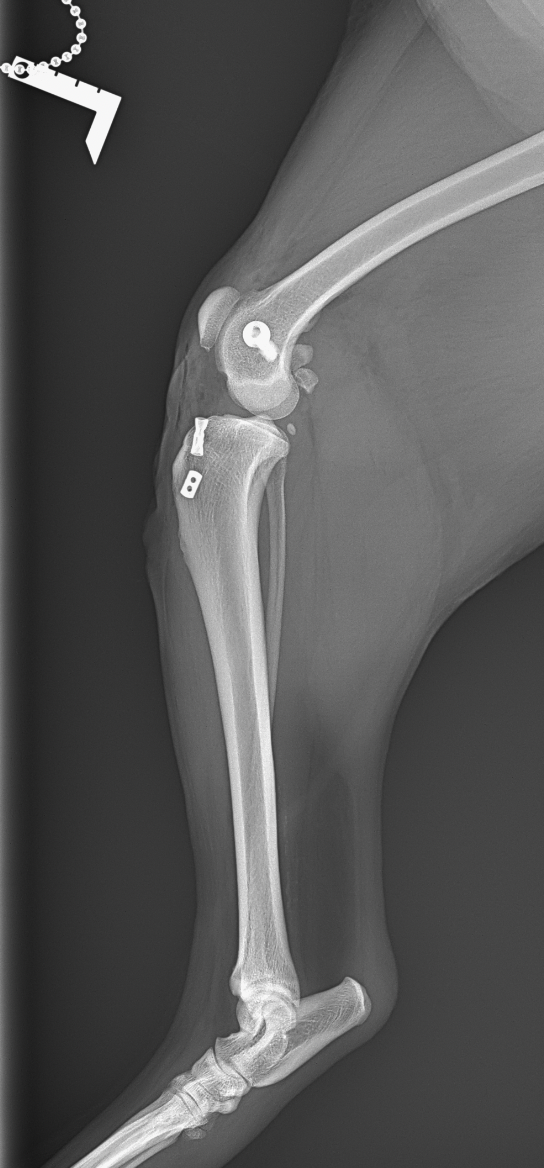

本症例は高齢であり、手術侵襲を最小限に抑える必要がある。また、手術時間を短縮することが望ましい。以上を考慮し、関節外安定化法であるラテラルスーチャー法を選択した。関節包切開後、前十字靭帯の完全断裂を確認。内側半月板に損傷を認めたため、損傷部位を部分切除。

ラテラルスーチャー設置:

・外側大腿顆後方(Fabella近位)に4.0横穴付きスクリューを埋入。

・脛骨内側にエンドボタンを装着、ナイロン糸を8の字状に通過

・膝関節を軽度屈曲位で適切なテンションをかけてチタンクランプで締結。